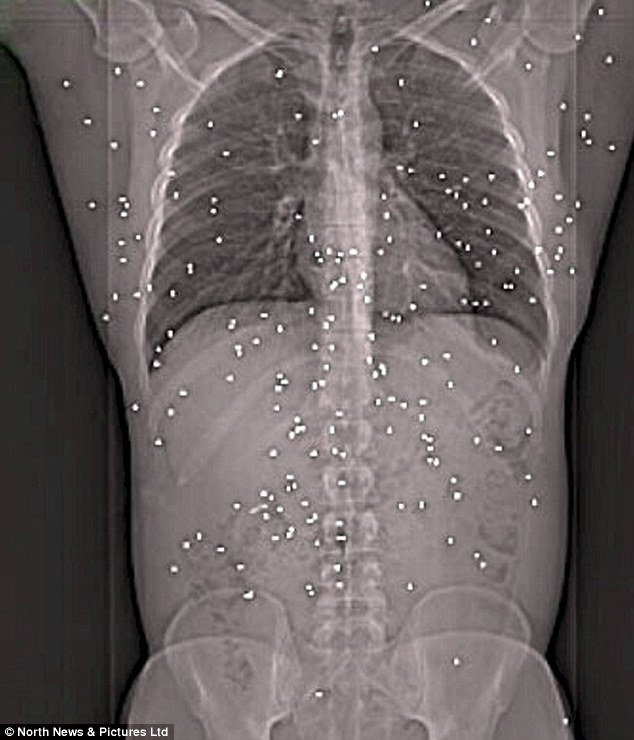

打在鬼身上大概是這樣